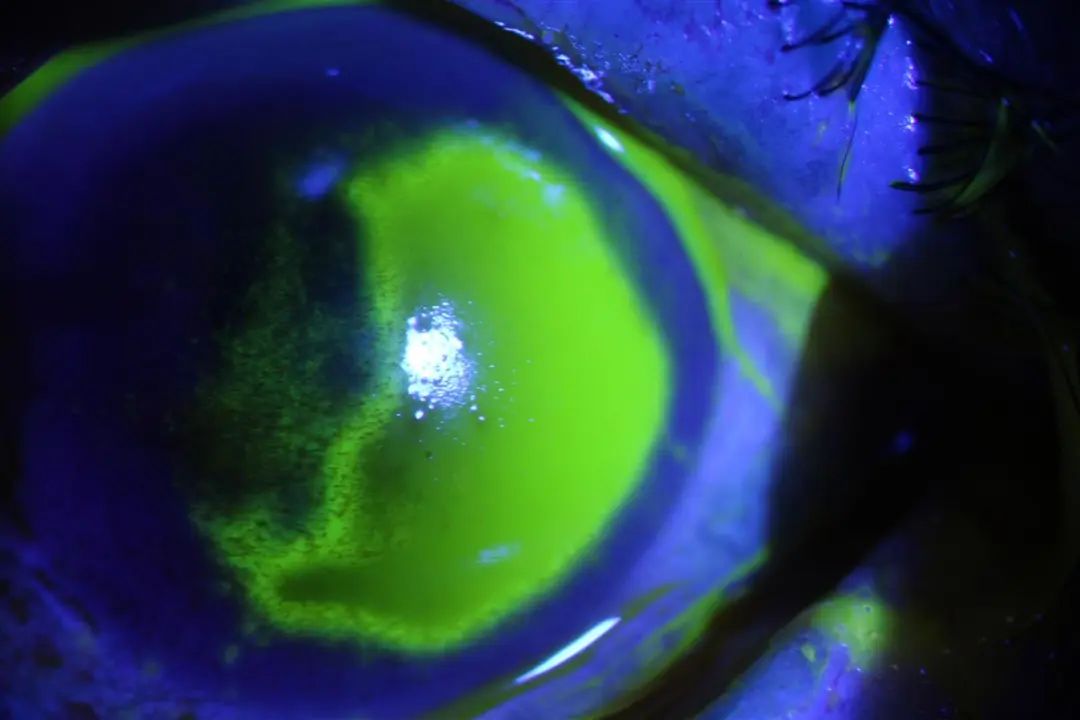

夏朝霞立即给王姨安排了角膜荧光染色拍照检查。检查结果发现,王阿姨结膜充血,角膜损伤,角膜上皮大片剥脱。

就诊前左、右眼检查结果